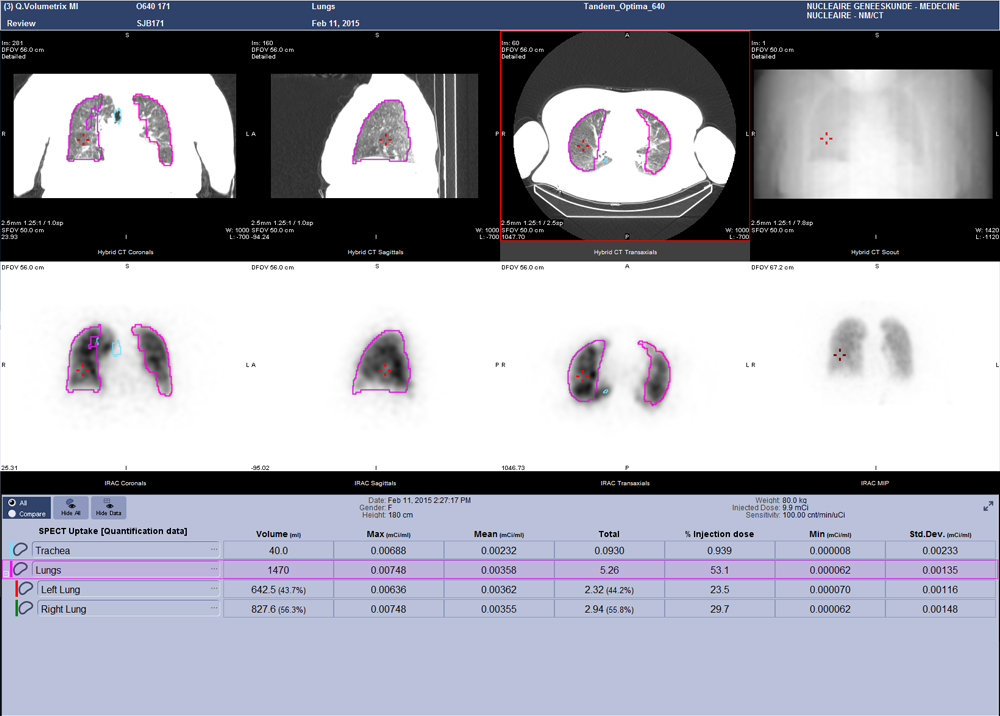

Q.Volumetrix MI is an Xeleris 4 DR application that integrates SUV measurements directly into the volume viewer. It allows you to see both the image and the SUV simultaneously instead of having to switch back and forth between two separate applications.

Then, with SmartConsole, your quantitative SPECT/CT studies are automatically transferred directly to the PACS or other pre-defined DICOM destination. These resource-saving improvements allow you to expand your services without breaking your schedule.